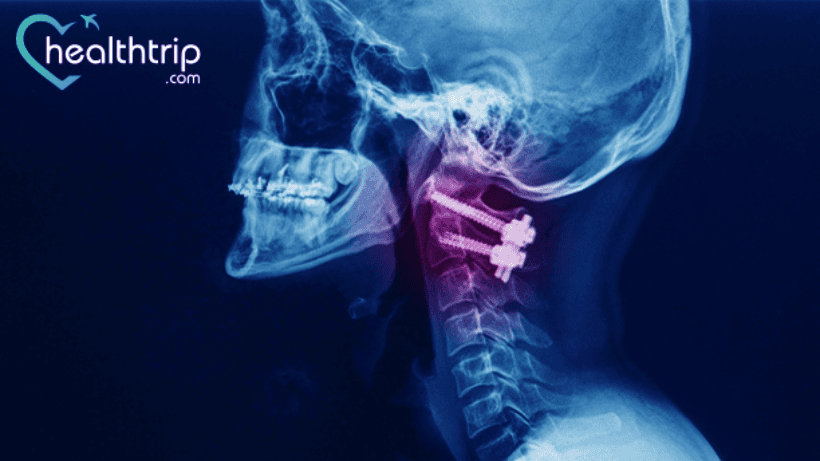

ከእንዲህ ዓይነቱ የተለመደ የአከርካሪ ውህደት ቀዶ ጥገና አንዱ የፊተኛው የሰርቪካል ዲስክክቶሚ እና ፊውዥን ቀዶ ጥገና (ACDF) ነው።.

የማኅጸን መገጣጠሚያ ቀዶ ጥገና ለብዙ ሰዎች በጣም ስኬታማ ሆኗል. በቀዶ ጥገናቸው ጥሩ ውጤት ያላገኙ ሰዎች የአንገት ህመም፣ የአንገት አለመረጋጋት እና የአጥንት መነቃቃት አጋጥሟቸዋል።. በአንዳንድ ሁኔታዎች, ያልተሳካውን ለመጠገን ተጨማሪ ውህደት እንደሚያስፈልግ ተመክረዋል.

እንደ ባለሙያው የአከርካሪ ቀዶ ጥገና ሀኪም፣ ያልተሳካ የማኅጸን መገጣጠሚያ ቀዶ ጥገና ምልክቶች የሚከተሉት ናቸው።

- ከቀዶ ጥገና በኋላ የሲናስ ራስ ምታት እና የአቀማመጥ ችግሮች: ይህ በሃርድዌር ውድቀት ወይም በቀዶ ጥገና ምክንያት የነርቭ ጉዳት ምክንያት ሊከሰት ይችላል።. ምክንያቱ ተጣርቶ ውድቅ መደረግ አለበት።. ከዚህ በመቀጠል ውህደቱ የከፋ የአንገት አለመረጋጋት ያስከተለ ወይም አለመኖሩን ለማወቅ ባለሙያዎቻችን በአጠገቡ ባሉት የአንገት ክፍሎች ላይ ያተኩራሉ።.